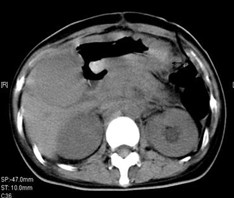

女,40歲,2006年10月底確診為胃腺癌(皮革胃),腹腔淋巴結(jié)轉(zhuǎn)移;2006年11月外科手術(shù)時(shí)見(jiàn)腹腔廣泛轉(zhuǎn)移(粘連),病灶無(wú)法切除(下圖1a,b),預(yù)期生存期低于3個(gè)月;留置(胃)造瘺管。2006年12月開(kāi)始今又生聯(lián)合化療治療,今又生2×1012VP,室溫下自行融化后加入到100ml生理鹽水中,30~40分鐘內(nèi)靜脈滴注完畢,1/次/周,連續(xù)使用6周。今又生給藥三天后靜脈化療。2007年7月外科手術(shù)拔除造瘺管;2007年9月隨訪,患者狀況良好,無(wú)復(fù)發(fā)。

1a 治療前胰腺體部和主動(dòng)脈前方淋巴結(jié)較多較大,胃底和體部較厚僵硬

1b治療后 淋巴結(jié)較少并縮小,胰腺和主動(dòng)脈之間脂肪間隙恢復(fù)清晰,胃底和體部較前變薄,柔軟